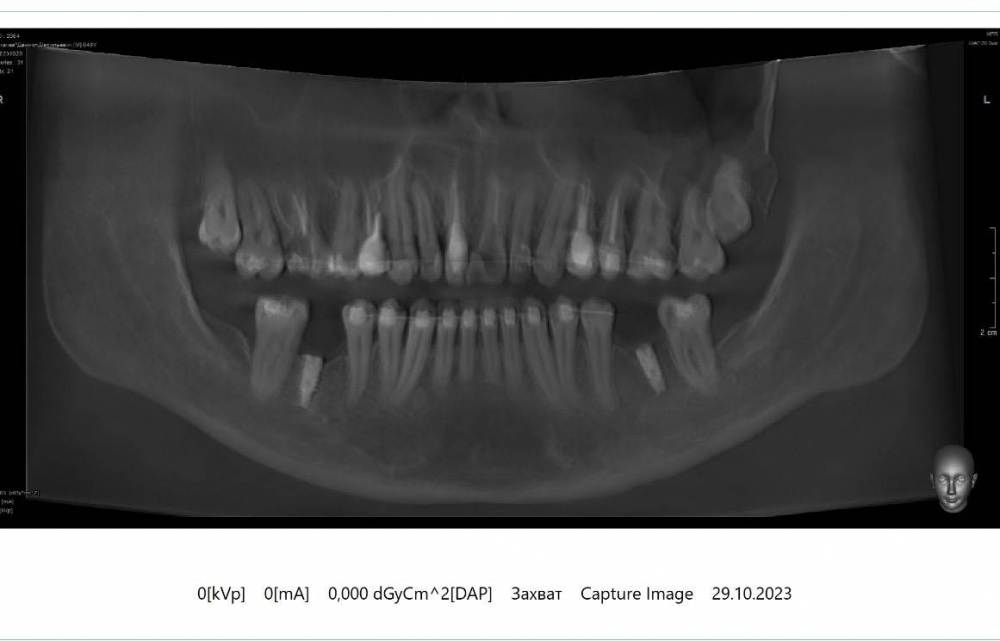

saravar Опубликовано 7 ноября, 2023 Поделиться Опубликовано 7 ноября, 2023 Добрый вечер. Несколько лет назад поставил два имплантата. Израиль. Параллельно ношу брекеты. Поменял клинику. Так как врач уехал в Москву. Пришел по рекомендации в новую клинику. Говорят имплантаты стоят криво. Предлагают удалять и ставить заново. Возможно с какими-то хирургическими манипуляциями. собственно вопрос. Реально ли обойтись без удаления и поставить коронки на эти. При условии, что продолжаю лечение у ортодонта и зубы можно двигать. и второй вопрос. Есть ли смысл удалять две верхние восьмерки, при условии, что верхнюю шестерку будут удалять. (Реально ли после удаления задвинуть восьмерку с помощью брекетов) возраст 39 Ссылка на комментарий

red_butler Опубликовано 8 ноября, 2023 Поделиться Опубликовано 8 ноября, 2023 Здравствуйте, показаний к удалению имплантов не вижу 1 Ссылка на комментарий

Bier Опубликовано 8 ноября, 2023 Поделиться Опубликовано 8 ноября, 2023 можно было поставить лучше, но как есть - не сильно критично. Можно отпротезировать. 1 Ссылка на комментарий

Doc Опубликовано 9 ноября, 2023 Поделиться Опубликовано 9 ноября, 2023 Согласен с предыдущими ораторами. Ситуация не самая прекрасная, но терпеть можно. Ссылка на комментарий